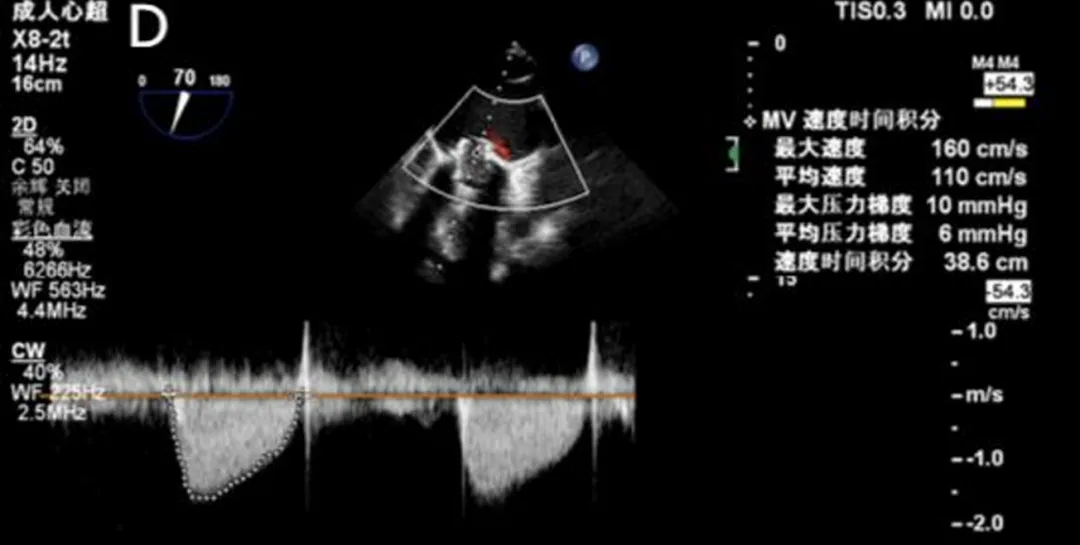

2025年6月4日,在全身麻醉下,通过TEE和荧光镜引导进行手术。通过右颈内静脉建立临时起搏。经左前外侧小切口暴露第五肋间隙,使用双重荷包缝合固定心尖;静脉注射肝素使活化凝血时间(ACT)>250秒。心尖穿刺后,先使用软导丝穿过主动脉瓣口,随后更换为Amplatz超硬导丝(波士顿科学公司)。在快速起搏(180次/分)下,使用18mm球囊对主动脉瓣生物假体进行预扩张。选择21mm ScienCrown瓣膜,旋转手柄将瓣膜从输送系统中逐步释放(视频1)。瓣膜成功植入后,无错位或瓣周漏(PVL)(图2B及视频2)。TEE显示主动脉瓣平均跨瓣压差为6mmHg,无瓣周漏(图2C及D)。随后,使用硬导丝穿过二尖瓣生物瓣进入左心房(视频3)。在快速起搏(180次/分)下于二尖瓣位置植入25mm ScienCrown瓣膜(图2E及视频4)。TEE显示二尖瓣平均跨瓣压差为5mmHg,瓣叶运动正常,无瓣周漏(图2F)。术后荧光检查显示两枚瓣膜均位置良好(图2G)。术后第一天床旁TTE显示二尖瓣压差2.52mmHg,流速0.76m/s;主动脉瓣压差13.39mmHg,流速1.7m/s,提示轻度主动脉瓣狭窄(AS)和正常二尖瓣功能(图3)。患者心功能改善至NYHA II级,并在术后第5天出院。

图2. 使用ScienCrown瓣膜进行经心尖主动脉瓣和二尖瓣ViV手术。A:18mm球囊对主动脉瓣进行预扩张。B:成功植入21mm ScienCrown瓣膜,显示无瓣周漏。C:植入后TEE确认无瓣周漏。D:术后TEE记录主动脉瓣平均跨瓣压差为6mmHg。E:二尖瓣位置25mm ScienCrown瓣膜的理想释放。F:植入后TEE评估显示二尖瓣平均跨瓣压差为5mmHg。G:术后影像学检查显示两枚植入假体瓣膜的位置及形态均正常。